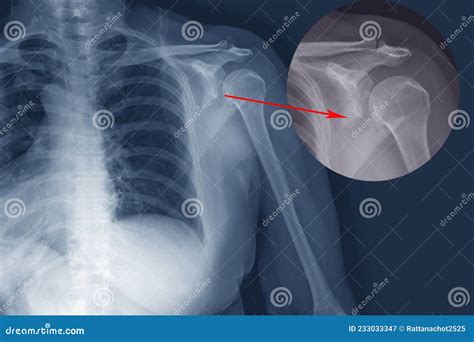

Diagnosing a displacement bone fracture typically involves a combination of physical examination and imaging tests. The diagnostic process usually includes:

• Physical examination: A healthcare provider will assess the injured area for pain, swelling, deformity, and loss of function.

• X-rays: These are the primary imaging tool used to visualize the bone and determine the extent of the fracture and displacement.

• CT scans: For more detailed images, especially in complex fractures, a CT scan may be ordered.